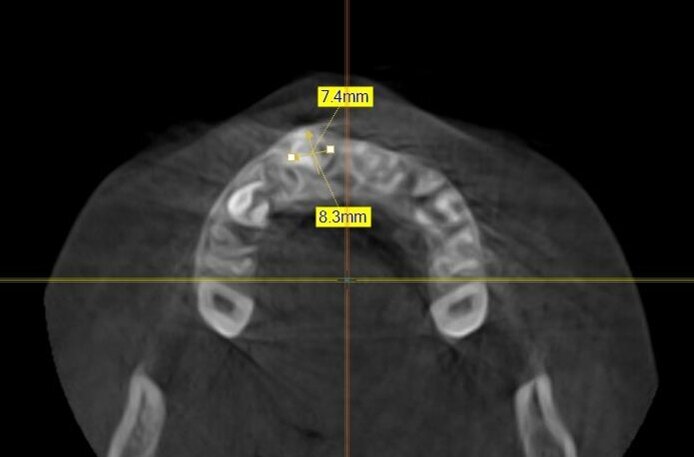

In seguito all’esame obiettivo e dopo aver preso visione dello studio radiografico del caso (effettuato mediante esami di 1° e 2° livello) si diagnostica la presenza di una neoformazione di dimensioni approssimativamente pari a 7,4 x 8,3 mm posizionata tra gli elementi 5.1 e 5.2 il cui aspetto è compatibile con quello di un odontoma (Figg. 2, 3). La presenza di questa neoformazione impedisce il normale tragitto eruttivo dell’elemento 1.1 che appare inoltre leggermente mesio-inclinato: questa condizione indica come terapia elettiva l’enucleazione chirurgica della massa neoformata e la contestuale cementazione di un attacco ortodontico per procedere al recupero dell’elemento ritenuto.

Fig. 3_Esame CBCT: proiezione assiale che evidenzia localizzazione e dimensioni della neoformazione.